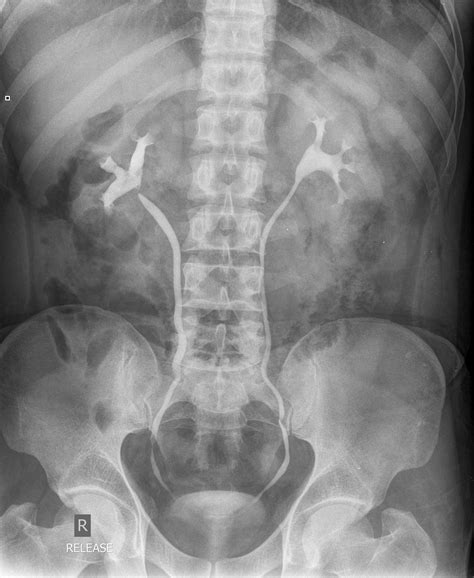

Title: - Intravenous Urography